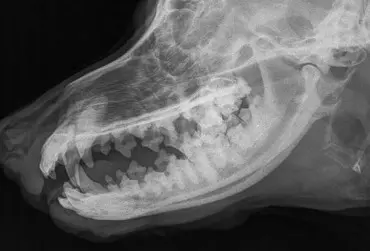

Kamienie ślinowe u psów – opis przypadku

Choroby ślinianek są rzadkie u psów. Najczęściej występującą nieprawidłowością jest mucocele. Do przyczyn tego zaburzenia można zaliczyć urazy, ciała obce lub kamienie ślinowe, dirofilariozę, nowotwory oraz przyczyny idiopatyczne. Do zaburzenia dochodzi również po zabiegach mandibulektomii. W artykule opisano przypadek psa z mineralizacją w okolicy odpowiadającej umiejscowieniu przewodu ślinianki przyusznej.